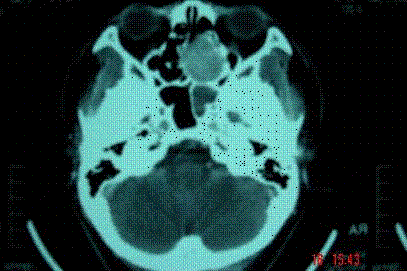

问题 病历摘要: 患者男,37岁,因右鼻塞伴涕中带血4个月入院,患者4个月前始右鼻塞,为间断性,偶有涕中带血,时有流脓性分泌物,并症状渐渐加重。但发病以来患者无头痛、面部麻木和疼痛,无复视及流泪,张口正常。检查:右侧鼻腔总鼻道可见表面光滑、质中、粉红色肿物,触之不易出血。鼻咽黏膜光滑,未见新生物和黏膜糜烂。颈部未及淋巴结肿大。 鼻腔鼻窦恶性肿瘤有哪些手术疗法?